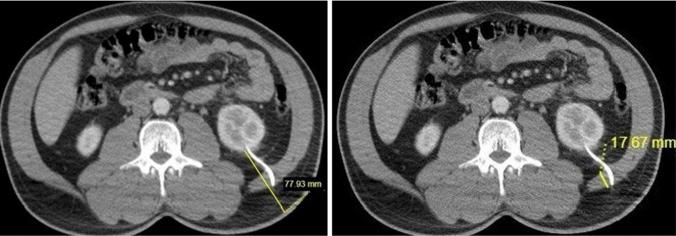

A retrospective review of 742 percutaneous nephrostomy (PCN) procedures carried out between June 2020 and June 2024 was conducted. Thirty-eight patients with spontaneous NCD were assigned to the dislodgement group, and 38 matched controls were selected using propensity score matching.. Key measurements included cortex-to-skin distance, paravertebral muscle area, psoas muscle area, subcutaneous fat thickness, and renal parenchymal thickness.

Patients with NCD were similar in age and sex. No significant differences were observed in subcutaneous fat thickness, muscle thickness, or renal parenchymal thickness between the groups. However, cortex-to-skin distance was significantly shorter in the NCD group (p = 0.001). ROC analysis identified an optimal threshold of 46.65 mm for cortex-to-skin distance, with a sensitivity of 92.1%, specificity of 39.5%, and a positive predictive value of 60.3% (AUC = 0.67).

对2020年6月至2024年6月期间进行的742例经皮肾造瘘术(PCN)进行回顾性研究。38例发生自发性NCD的患者被分配到移位组,并使用倾向得分匹配法选择38例匹配对照。关键测量指标包括皮质到皮肤的距离、椎旁肌面积、腰大肌面积、皮下脂肪厚度和肾实质厚度。

NCD患者在年龄和性别上相似。两组之间在皮下脂肪厚度、肌肉厚度或肾实质厚度方面未观察到显著差异。然而,NCD组的皮质到皮肤的距离明显更短(p = 0.001)。ROC分析确定皮质到皮肤距离的最佳阈值为46.65毫米,灵敏度为92.1%,特异性为39.5%,阳性预测值为60.3%(AUC = 0.67)。